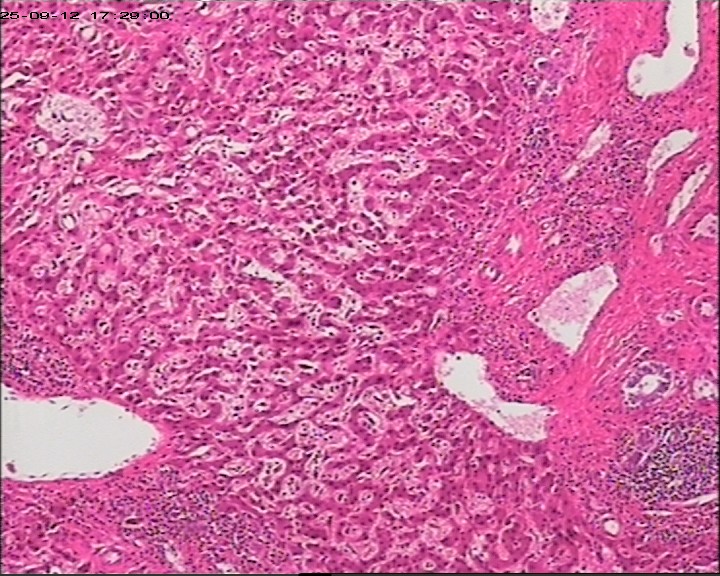

性别年龄47岁临床诊断肝占位性质待查,肝棘球蚴病?

大体所见肝组织一块,大小为20*18*15cm,切面多房囊性,部分内含坏死样物。

建议:描述性病理诊断!(感觉符合棘球蚴病病理改变,但未见明显的直接证据!)

大体检查有没有看到粉皮样的角质膜?取角质膜在镜下找到头节有助于诊断。